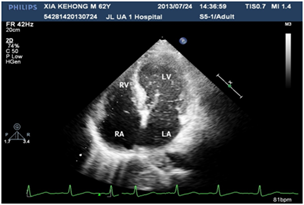

Figure 1 Micro-bubble appears in RA, RV, delayed appearance in LA, LV.

A 60years old male, known case of diabetes mellitus, hypertension and alcoholic hepatic cirrhosis had exercise induced chest discomfot, shortness of breath, fatigue and lips cyanosis half a year ago, which relieved at rest. But later he became serious for one week and visited our department for further management. He had no cough, fever, dizziness, headache or bleeding history from any site. He had pituitary adenoma, which was surgically removed 6years ago. He denies history of chronic infections such as tuberculosis or actinomycosis or family history of hereditary hemorrhagic telangiectasis (HHT). Physical examination revealed cyanosis of the face and lips, clubbing, numerous spider naevi on neck, chest and palm and no telangiectasia on mucosa or fundi. His blood pressure was 130/80mmHg, heart rate was 76beats/min and resting oxygen saturation was 66% in room air. A grade 1/6 soft systolic murmur was heard on the upper left sternal border and clear lungs sound. There were no bruits. The hemoglobin was 11.5gm/dL and the hematocrite was 35.5gm/dL. Arterial blood gas analysis showed Pao2 64mmHg on room air and after 100% of oxygen 74mmHg with Paco2 41mmHg and PH-7.35. Chest radiography and electrocardiogram did not show any abnormalities. Pulmonary function test showed alveolar dispersion function severely reduced. Transthoracic echocardiography showed normal findings (No PFO/ASD/VSD/PDA detected). We performed contrast echocardiography using agitated saline. A delayed appearance of a substantial amount of micro-bubbles in the left atrium greater than three cardiac cycles after appearance in the right atrium and ventricle (Figure 1) which was suggestive of pulmonary arteriovenous fistula. The delayed appearance and a large amount of micro-bubbles in the left atrium preclude the intracardiac shunting resulting from a patent foramen ovale (PFO) or arterial septal defect (ASD). Interestingly, the density of micro-bubbles was the same in the left and right cardiac chamber even after 10 cardiac cycles (Figure 2 & 3) and when the injection stopped, there were micro-bubbles in the left cardiac chambers meanwhile none in the right cardiac chambers (Figure 4). Because the hepatic function of the patient was in compensatory period, we gave him oxygen-inhalation and beta-blockers in order to decrease the oxygen demands and to lower the portal vein pressure. Moreover, he was advised to avoid sudden standing. The cyanosis improved, and the patient was discharged from the hospital and on regular follow-up. The patient was advised for pulmonary angiography but refused.